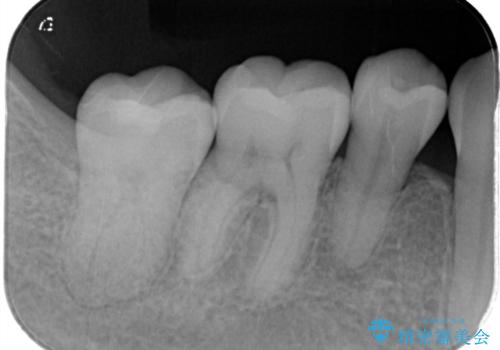

昔の被せ物が取れてしまった セラミックアンレーで治療

- 昔に治療した金属のかぶせものが取れてしまい来院されました。他院にて応急処置がされており、レントゲンなどで現状を把握した後、切削量が比較的少なく短期間で終了するセラミックアンレーにて治療いたしました。

経過良好で噛み合わせなども問題なく、前の被せ物より綺麗な被せ物がセットされ、非常に満足いただけました。